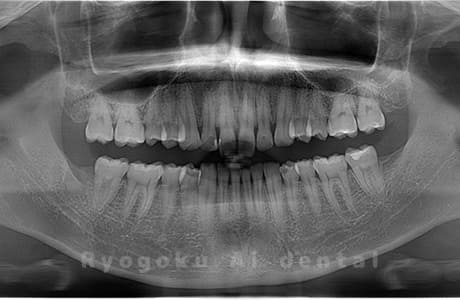

真っ直ぐ生えている親知らず

親知らずが真っ直ぐ生えているタイプです。

このタイプは真っ直ぐ生えていて咬み合わせに問題がなければ、抜歯しないケースもあります。ただし、虫歯になっていたり、痛みがあったり、咬み合わせが悪かったりすると抜歯をおすすめします。